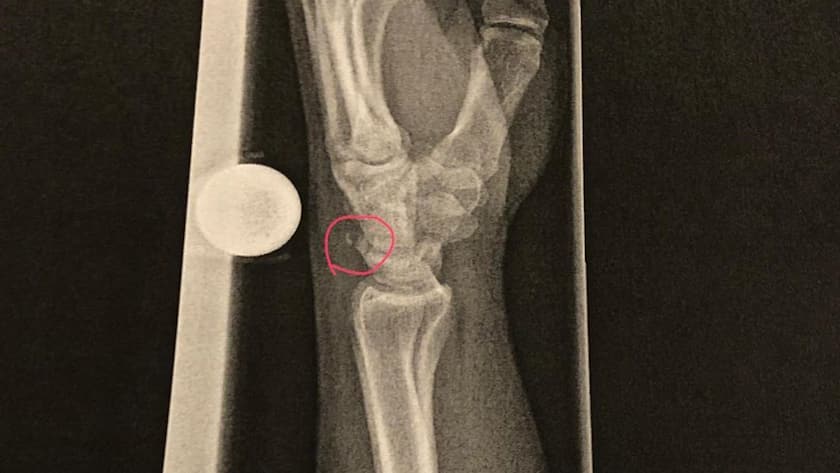

Über das ganze Jahr 2024 betrachtet, registrierte die Suva die meisten Sportunfälle beim Fussballspielen (29 000 / 26 % aller Sportunfälle), beim Skifahren (14 000 / 13 %) sowie beim Biken/Mountainbiken (5000 / 4,6 %). Dabei gibt es geschlechtsspezifische Unterschiede. Bei den Männern entspricht die Reihenfolge der häufigsten Sportunfälle dem Gesamtergebnis (Fussball (31 %), Skifahren (11 %), Biken (5 %)), während bei den Frauen die meisten Unfälle beim Skifahren (19 %) passierten, gefolgt vom Bergwandern (8 %) und Fussballspielen (7 %, v.a. bei Frauen unter 30 Jahren). Die häufigsten Verletzungen betrafen Knie, Fussgelenke und Schultern.